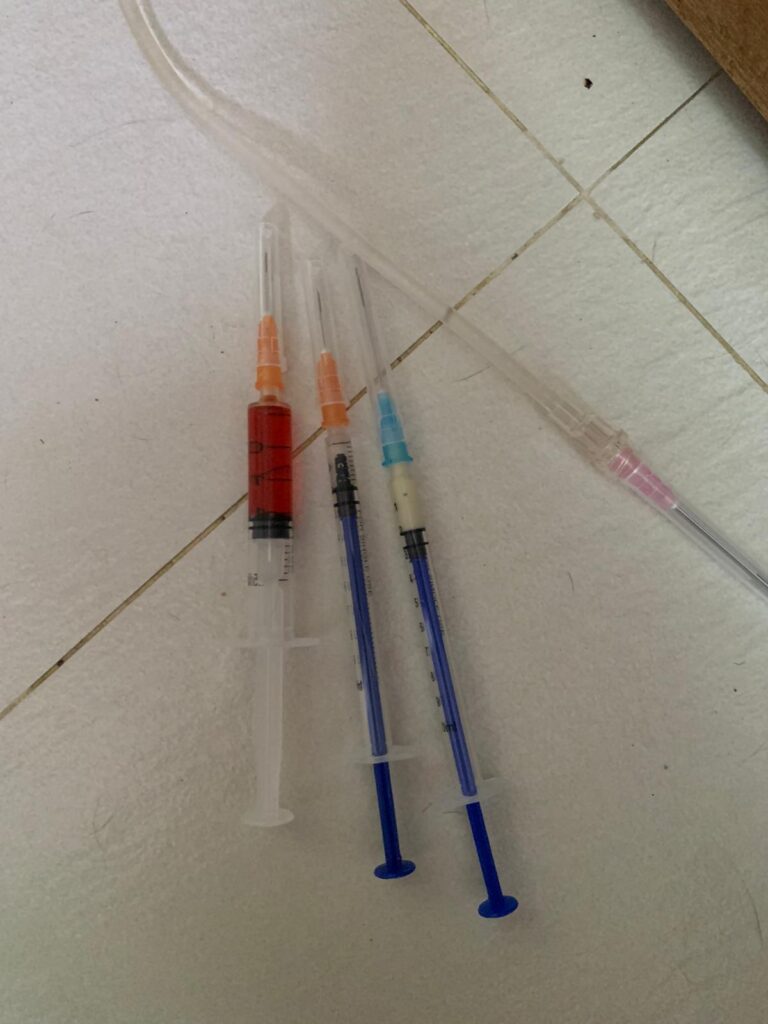

Prepare his fercosang jab to be given Tmr

11Am+: given Subcut, b com n b12 and fercosang. He is still on f patch, wipe his face

Morning: Subcut

Morning: major cleaning day. Subcut him n given b12 b com jab. His f patch drop off le. Given bupre. Still love selar

Morning: looks in pain. Give Subcut and bupre. I don’t have f patch in 5G. scanned on 19.4.24 no m/c.

Morning: got helper in to cut nails, steam bath and clean ears. She can handle him alone. Given Subcut bupre n put on f patch for him.

Morning: got 2 helpers in to clean up and for him: cut nails, clean ears and steam brush fur. His f patch if off, given Subcut and bupre jab

Morning; both eyes discharge look bad, clean up and put banocin on his ear. Will Subcut him and give Clav jab and bupre n put on new f patch for him

Morning: f patch intact. Apply banocin powder on ear. Still look got blood clog, didn’t bleed further. Given 5th and last Clav jab.

Morning: Subcut n on regular med and place new f patch n still given bupre

10am+: b4 I Subcut n give painkiller still eating ok. Subcut and given b12 b com bupre and put on a f patch (end 1.3.24)

Morning: looks in pain. F patch still on. Given Subcut n Buprenophine.

Morning: alr in more regular bupre but today looks much more in pain. Tmr I need to give him f patch also

11Am+: given bupre jab and place a f patch on his left ear.

Noon: 3.91kg – lose 210g in 1 week. Subcut him w B12 n b com. N bupre. More vocal but in pain can’t think of reason to go clinic other than status check

12pm+: 4.12kg – gain 50g in 2 months. On regular maintenance Subcut and bupre n b12. and dental care

Morning: given Subcut w b12 b com. N bupre

Morning: didi constipated, saw him in 2 bins, trying to squeeze out something n can’t n he try to rub on floor – aren’t that pushing that piece in? I help him push out the 2cm piece 5/10, and he go to bin 03 and poo out another 12cm. So is that piece stuck n he is so uncomfortable. Subcut him w bupre also. His f patch still on. Can tear off soon. Need to buy more

Just status update: Today Subcut n given b12 b com also. Given bupre and fercosang also. eye more discharge. Pain. Shave his ear and place a f patch also.

Morning: Subcut w b12 and Buprenophine

Morning: Subcut w b12 and Buprenophine

Morning: Subcut w b12 and bupre.